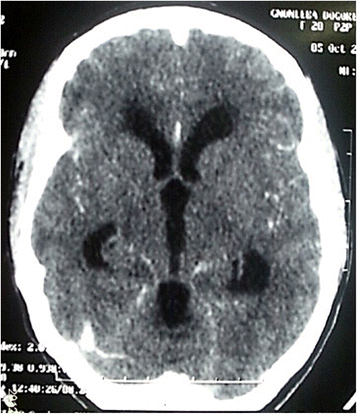

A 20 years old female patient with no medical history was referred to our department for 1 month progressive onset of intense headache. On clinical examination, the patient was complaining of worsening headache associated with vomiting. However, no neurologic deficit was noticed. The CT scan revealed an important dilatation of lateral, third and fourth ventricle (Fig. 1). A ventriculoperitoneal shunt was inserted as an urgent treatment of the intracranial high pressure. The outcome was favorable and the patient was discharged 05 days later.